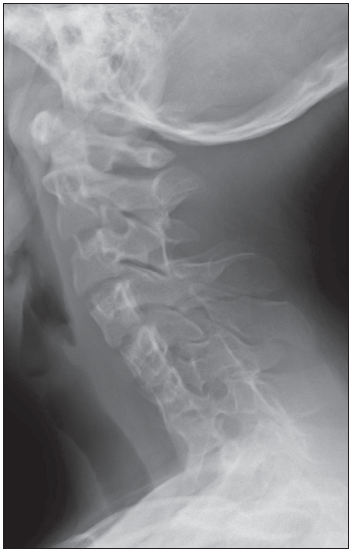

Radiograph of cervical spine as shown.

Lateral flexion-extension radiographs of the cervical spine confirm the diagnosis and establish the range of motion of each open interspace.2 A lateral radiograph of the skull will demonstrate occipitocervical abnormalities.10 MRI of the cervical cord and craniocervical junction is indicated before any orthopedic procedure and whenever neurologic symptoms or signs are present in the upper extremities.17